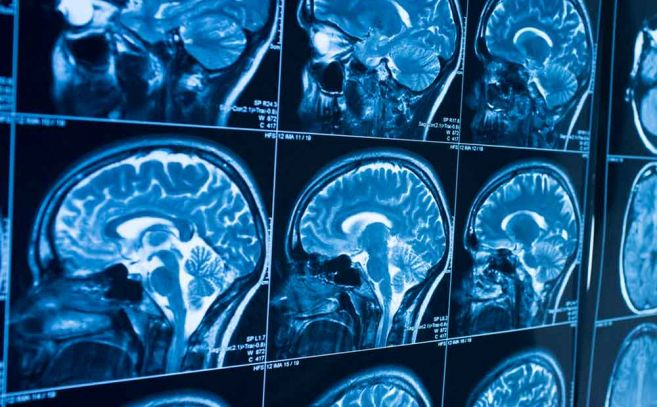

À luz desses dados, o trabalho do Dr. Garry P. Nolan , professor de patologia na Faculdade de Medicina da Universidade de Stanford, torna-se particularmente relevante. Nolan foi contatado por agências de inteligência e defesa para analisar exames de ressonância magnética de aproximadamente cem indivíduos principalmente pilotos, militares e trabalhadores da indústria aeroespacial que relataram sintomas neurológicos após o que descreveram como encontros próximos com UAPs (Fenômenos Aéreos Não Identificados). Nessas imagens, o pesquisador encontrou padrões indicativos de doença da substância branca , um termo médico para cicatrizes cerebrais semelhantes às observadas em casos de esclerose múltipla . Essas áreas brancas, resultado de uma resposta imunológica que deixa tecido nervoso morto ou cicatrizado, apareceram dispersas por regiões do cérebro onde as funções motoras e cognitivas são cruciais.

Além disso, Nolan e sua equipe observaram que muitos desses casos compartilhavam uma característica incomum: conectividade neuronal aumentada entre estruturas cerebrais internas — o núcleo caudado e o putâmen — que não é tipicamente vista na população em geral. Essa hiper conectividade levanta questões fascinantes: esses indivíduos têm predisposição genética para perceber eventos atípicos ou é o próprio encontro que desencadeia alterações neurológicas? Alguns dos participantes já haviam apresentado essas características em estudos realizados antes do suposto encontro, sugerindo que uma combinação de predisposição neurológica e respostas fisiológicas únicas pode estar envolvida.